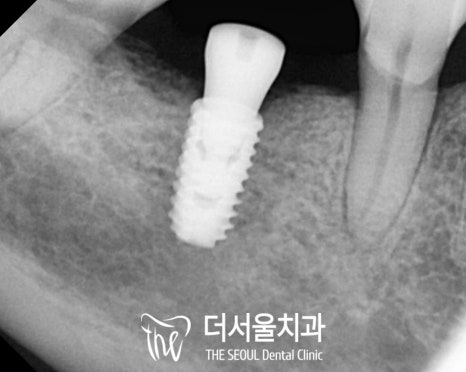

상하악의 해부학적 구조를 피해

안전하게 식립을 마친 모습입니다.

픽스처의 고정이 끝나고 나면

뼈와 단단하게 잘 붙었는지

고정력 측정기를 이용하여

수치를 확인합니다.

주변으로 하얗게 치조골이

잘 차올랐다면